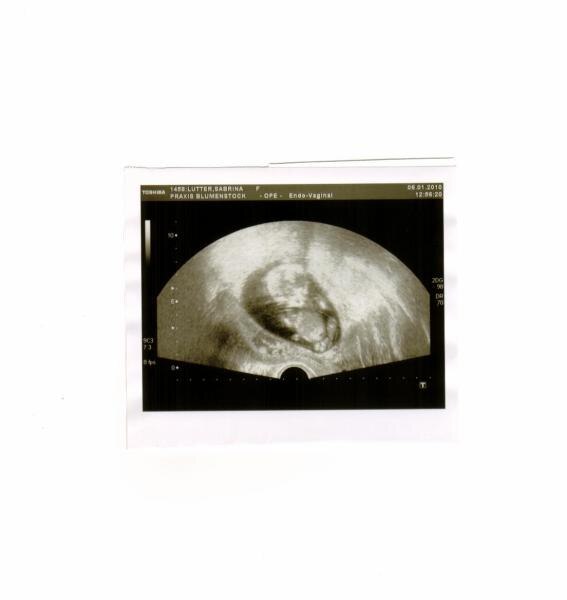

Baby ist 8 cm groß,keine aufälligkeiten alles super meinte sie.FROI FROI

Na ja habe von ihr 3 Bilder bekommen vom Baby

Das ist ja ein Yoga-Krümel....sitzt schön entspannt im Schneidersitz ... Süß!